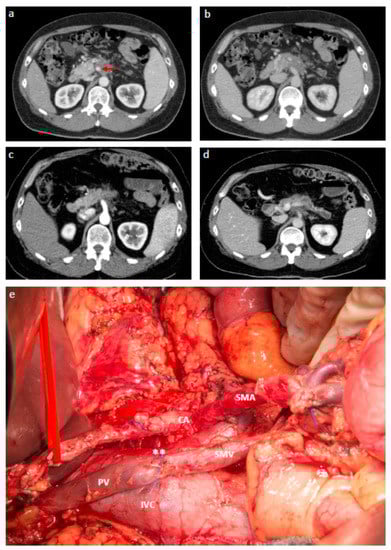

- Hackert, T.; Strobel, O.; Michalski, C.W.; Mihaljevic, A.L.; Mehrabi, A.; Muller-Stich, B.; Berchtold, C.; Ulrich, A.; Buchler, M.W. The triangle operation-radical surgery after neoadjuvant treatment for advanced pancreatic cancer: A single arm observational study. HPB 2017, 19, 1001–1007. [Google Scholar] [CrossRef] [PubMed]

- Inoue, Y.; Saiura, A.; Yoshioka, R.; Ono, Y.; Takahashi, M.; Arita, J.; Takahashi, Y.; Koga, R. Pancreatoduodenectomy with systematic mesopancreas dissection using a supracolic anterior artery-first approach. Ann. Surg. 2015, 262, 1092–1101. [Google Scholar] [CrossRef] [PubMed]

- Klompmaker, S.; van Hilst, J.; Gerritsen, S.L.; Adham, M.; Teresa Albiol Quer, M.; Bassi, C.; Berrevoet, F.; Boggi, U.; Busch, O.R.; Cesaretti, M.; et al. Outcomes after distal pancreatectomy with celiac axis resection for pancreatic cancer: A pan-european retrospective cohort study. Ann. Surg. Oncol. 2018, 25, 1440–1447. [Google Scholar] [CrossRef] [PubMed]

- Klompmaker, S.; Peters, N.A.; van Hilst, J.; Bassi, C.; Boggi, U.; Busch, O.R.; Niesen, W.; Van Gulik, T.M.; Javed, A.A.; Kleeff, J.; et al. Outcomes and risk score for distal pancreatectomy with celiac axis resection (dp-car): An international multicenter analysis. Ann. Surg. Oncol. 2019, 26, 772–781. [Google Scholar] [CrossRef] [PubMed]

- Yoshitomi, H.; Sakai, N.; Kagawa, S.; Takano, S.; Ueda, A.; Kato, A.; Furukawa, K.; Takayashiki, T.; Kuboki, S.; Miyzaki, M.; et al. Feasibility and safety of distal pancreatectomy with en bloc celiac axis resection (dp-car) combined with neoadjuvant therapy for borderline resectable and unresectable pancreatic body/tail cancer. Langenbecks Arch. Surg. 2019, 404, 451–458. [Google Scholar] [CrossRef] [PubMed]

- Takasaka, I.; Kawai, N.; Sato, M.; Tanihata, H.; Sonomura, T.; Minamiguchi, H.; Nakai, M.; Ikoma, A.; Nakata, K.; Sanda, H. Preoperative microcoil embolization of the common hepatic artery for pancreatic body cancer. World J. Gastroenterol. 2012, 18, 1940–1945. [Google Scholar] [CrossRef] [PubMed]